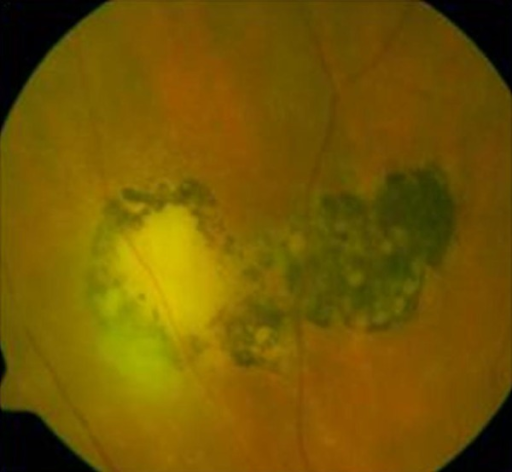

톡소플라즈마망맥락막염은 Toxoplasma gondii에 의한 가장 흔한 감염성 후포도막염입니다. 선천 또는 후천 감염 후 망막에 잠복하다가 재활성화됩니다. 기존 반흔 옆에 새로운 활성 병변(satellite lesion)이 나타나는 것이 전형적입니다.

- Headlight in the fog: 유리체 혼탁(fog) 속 밝은 황백색 활성 병변(headlight)

- Satellite lesion: 기존 맥락망막 반흔 옆에 새로운 활성 병변